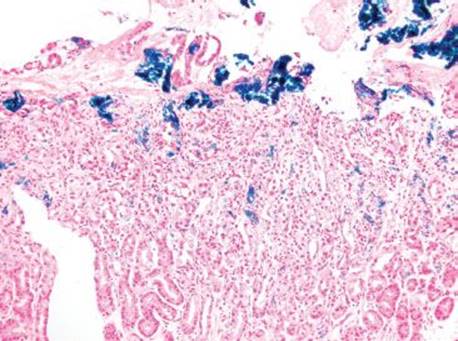

Figure 2.231 Iron pattern B/“iron pill gastritis”. In this dramatic case, coarse crystalline iron deposits are seen on the mucosa and within the luminal debris (arrowheads). A prominent reactive gastritis/gastropathy pattern is also seen in the background.

Gastric iron deposition is seen in up to 3.8% of upper tract biopsies (Fig. 2.228).23,24,183–185 In a study of 500 gastric biopsies, the deposition was demonstrated in three generalized patterns. Pattern A (also referred to as “nonspecific gastric siderosis”) was the most common subpattern and involved 2.2% of specimens (Figs. 2.229 and 2.230). This subpattern was associated with prior mucosal microhemorrhages, and the subtle depositions were predominantly identified within macrophages and stromal cells of the lamina propria. Pattern B (also referred to as “iron pill gastritis”) was seen in 0.8% of the biopsies and was consistently associated with ferrous sulfate therapy. This deposition was coarse and crystalline and predominantly identified in the extracellular and most superficial aspect of the biopsy (Figs. 2.231–2.234). In this subpattern, the background mucosa had a reactive gastritis/gastropathy pattern with erosions, ulcerations, and fibrino-inflammatory exudate common. In a separate study of 1,300 gastric biopsies, a similar “iron pill gastritis” injury pattern was detailed.184 This latter group reproduced the identical iron deposits in the laboratory by oxidizing ferrous sulfate tablets, providing clear evidence for the iron origin of these deposits. The mechanism of injury is a bit unclear in this subpattern. Some speculate that the iron pill has a direct caustic effect on the adjacent mucosa, whereas others suggest that the iron deposits may simply colonize previously injured mucosa. Pattern C (also referred to as “gastric glandular siderosis”) was the least common pattern, involving 0.6% of the specimens. This subpattern was associated with iron overload settings, such as hereditary hemochromatosis and multiple blood transfusions. The characteristic deposits were subtle, uniform, and identified in the deep antral and oxyntic glands (Figs. 2.235–2.239). The iron deposits can be highlighted blue with a Prussian blue iron special stain. Recognition is important to help prevent further injury and potential stricture formation (pattern B), to suggest pertinent iron overload evaluation (pattern C), and to avoid overdiagnosing the marked reactive epithelial change as dysplasia.

• Pattern B/“iron pill gastritis” features coarse, crystalline deposits in the extracellular space and most superficial aspects of the biopsy.